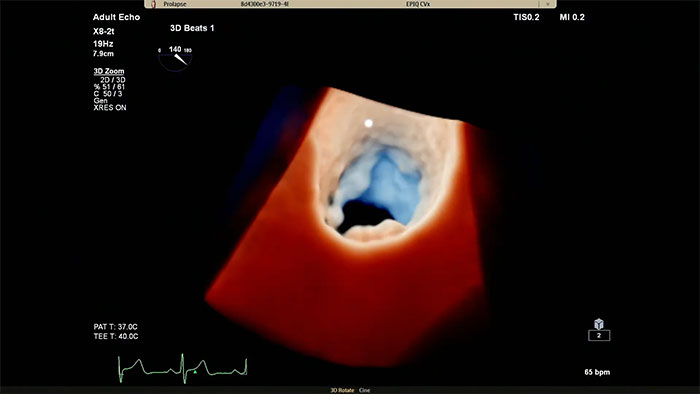

How can we make understanding mitral valve disease easier?

Philips Cardiac TrueVue on EPIQ CVx.

View enhanced visualizations of structures and flow with TrueVue Color

Visualize cardiac morphology using ultrasound with TrueVue Glass